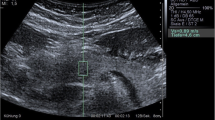

Conventional B-mode and 2-D SWE examinations were performed using LOGIQ P9 GE ultrasound system (GE Healthcare, Milwaukee, WI) using a 3.5- to 5-Mhz convex ultrasound transducer for all patients and controls. Examinations were performed and interpreted by two experienced radiologists (S.S.M. with 11 years’ experience and K.S.S. with 10 years’ experience) blinded to each other and to patients’ clinical and laboratory findings. The radiologists assessed patients separately and the mean score of both radiologists’ readings was taken for each patient.

The ultrasound transducer was placed in the epigastric region to visualize the entire pancreas. The pancreas was demonstrated in B-mode first, then 2-D SWE was performed in elastography display mode allowing 2-D elastography to be obtained. The ROI was placed on the pancreatic body ensuring that no blood vessels, capsule or pancreatic duct was located within it. The body was distinguished from the head by the confluence of the splenic and superior mesenteric veins. The tail was defined as the structure opposite the medial margin of the left kidney extending to the hilum of the spleen (identified by the splenic artery and vein) [1, 29].

The SWE measurements were automatically reported by the ultrasound machine by measuring 12 readings of elasticity at the ROI and calculating their median. Unacceptable shear wave measurements based on location or artifact were repeated. Reliable shear wave measurements were those with interquartile range (IQR) less than 30%.

Using conventional B-mode, no gross difference was found in the pancreatic echogenicity, homogeneity, contour and capsule sharpness between the studied children with type 1 diabetes and controls. Moreover, no pancreatic focal lesions or ultrasound evidence of pancreatitis was found in any of the subjects.

The mean SWE of the studied children with type 1 diabetes was 5.96±1.65 Kpa (range: 3.87–9.5), while that of the controls was 5.57±0.27 Kpa (range: 5.15–5.92), with no significant difference between the two groups (P=0.105). However, upon comparing the SWE between the studied children with recent-onset type 1 diabetes, those with long-standing type 1 diabetes and controls, a significant difference was found between the three groups (P<0.001). SWE was found to be highest in those with long-standing type 1 diabetes and lowest in those with recent-onset type 1 diabetes (P<0.001) (Table 2, Figs. 1, 2 and 3).